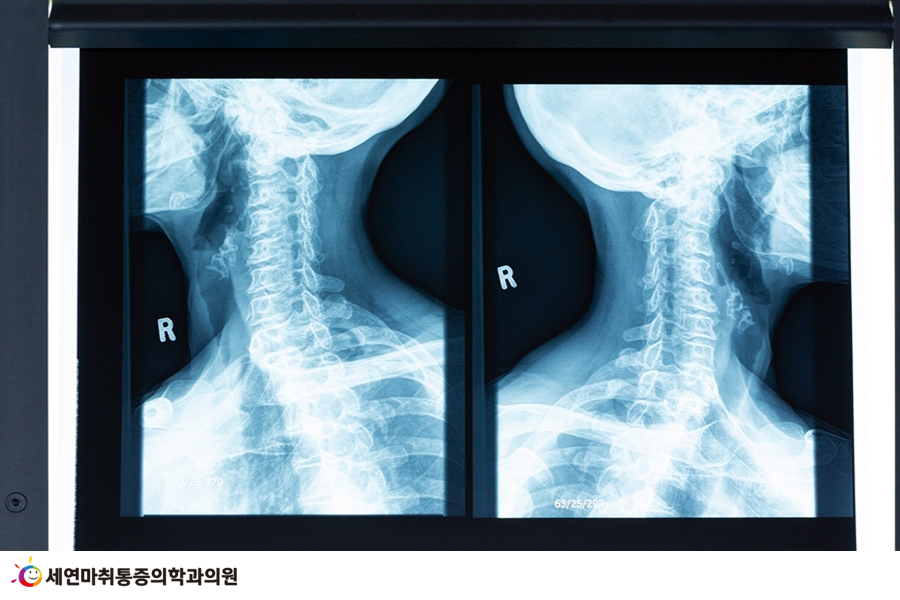

*일자목 원인 및 증상

일자목 증후군은 장시간 컴퓨터, 스마트폰 등 디지털 기기를 사용하거나 책상 앞에 오랫동안 앉아서 공부하는 학생 등에서 흔히 볼 수 있습니다.

목덜미의 뻐근함과 목 통증, 두통 등이 특징적이며 휴식을 취해도 증세가 나아지지 않거나 통증 빈도가 잦다면 일자목 증후군을 의심해볼 수 있습니다.

정상적인 경추는 C자 형태의 곡선을 이루지만, 일자목이 발병하면 곡선 전만의 형태가 아닌 일자가 되어 목이 어깨 선보다 앞으로 나와 신체 불균형과 통증을 초래합니다.

일자목은 뒷골 당김과 편두통, 목덜미 통증, 어깨결림과 운동 제한 등이 대표적인 증상이지만 제대로 치료하지 않으면 팔과 손 저림 등 합병 증상이 나타날 수 있고, 목뼈 사이에 위치한 척수 신경이 압박을 받아 목디스크 증상까지 나타날 수 있어 주의해야 합니다.